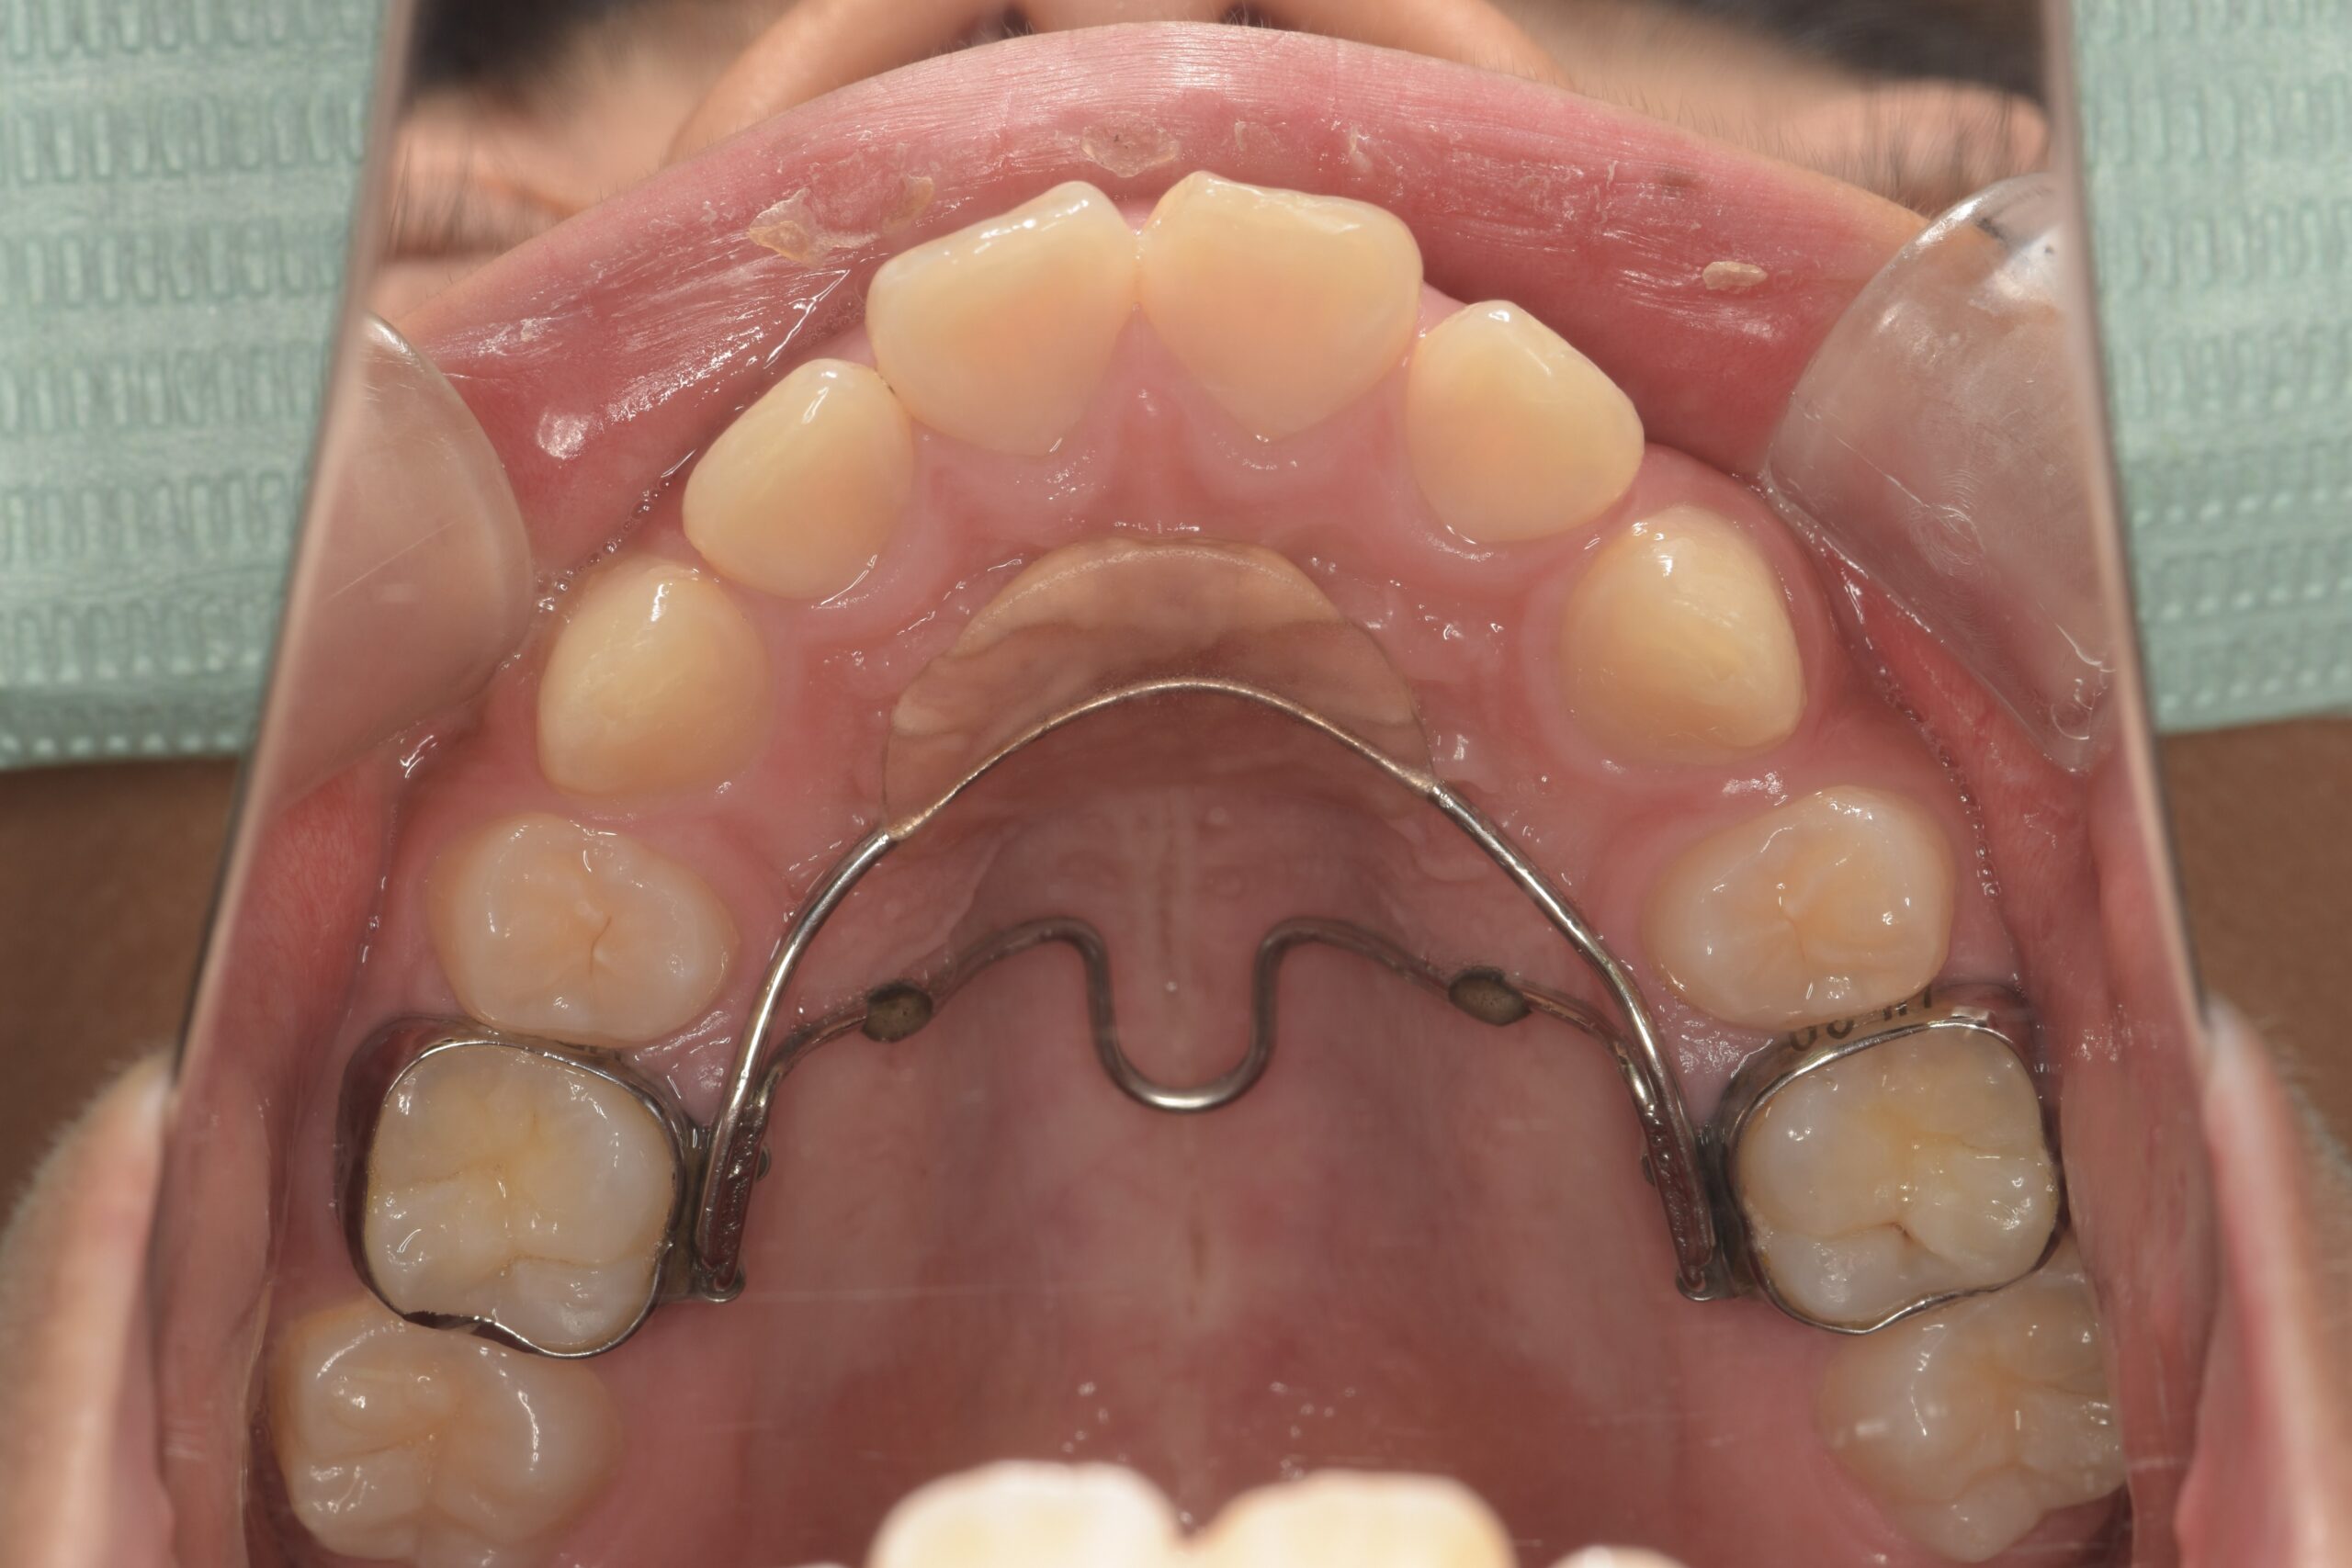

第一大臼歯が前に移動しないように装置で抑えます(上顎)

同じく装置で抑えます(下顎)

装置除去(上顎)

装置除去(下顎)